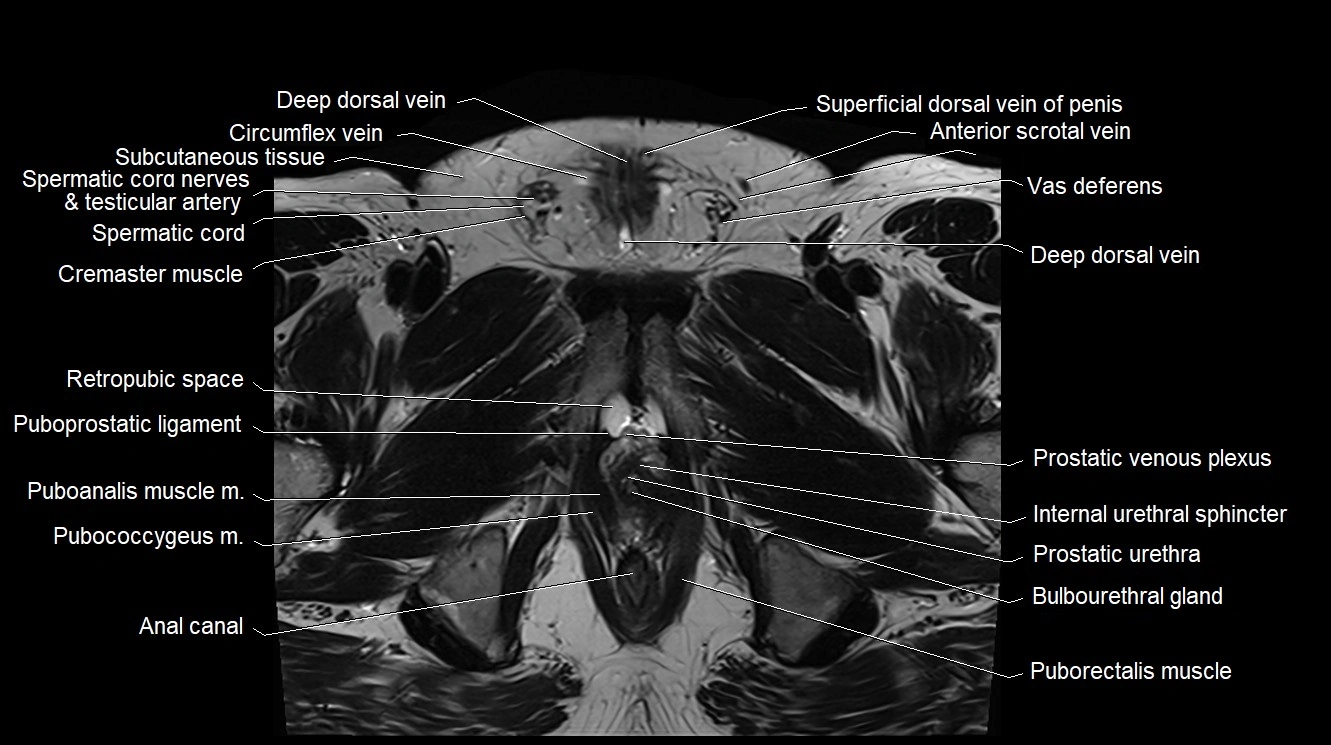

- Anal canal

- Bulbourethral gland (Cowperβs glands)

- Cremaster muscle

- Internal urethral sphincter (male)

- Prostatic urethra

- Puboanalis muscle

- Pubococcygeus muscle

- Puboprostatic ligament

- Puborectalis muscle

- Retropubic space

- Spermatic cord

- Spermatic cord nerves

- Superficial dorsal vein of penis

- Vas deferens